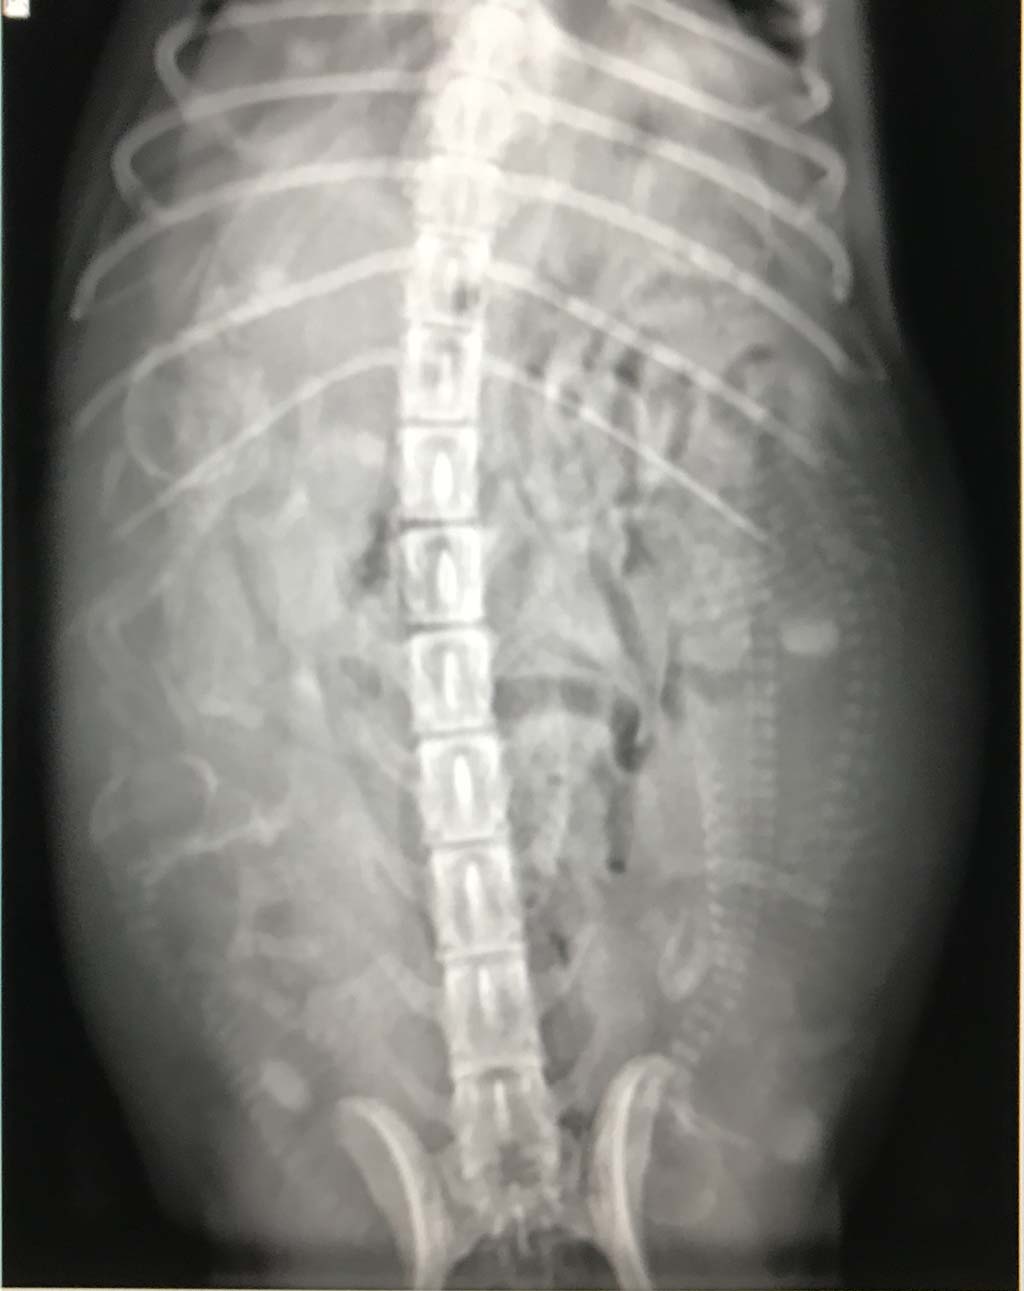

Die kommenden Tage werden wir Seven nun engmaschig überwachen und nicht nur Gewicht, sondern insbesondere ihre Temperatur. Wir hoffen natürlich auf eine reibungslose Geburt von den Zwergen. Wieviele es sind? Anbei die Aufnahmen von heute .... so kann jeder mal versuchen zu zählen ;-).

Seven am Tag 57 ihrer Trächtigkeit